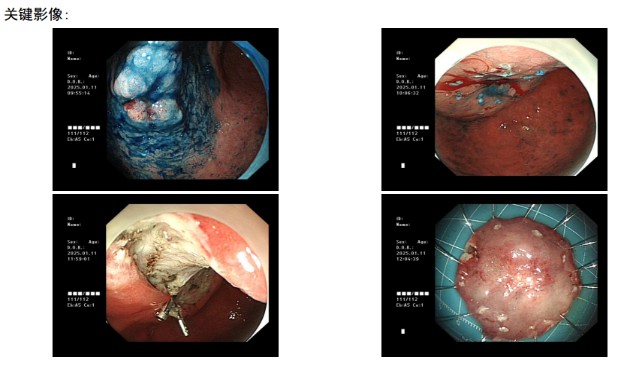

住院后�����,吳先生完善相關(guān)檢查,胃鏡檢查提示胃潰瘍伴癌變����,超聲內(nèi)鏡檢查提示粘膜層增厚明顯。消化內(nèi)科醫(yī)生團(tuán)隊(duì)針對此病例立即啟動(dòng)MDT多學(xué)科聯(lián)合會(huì)診���,建議吳先生行早期胃癌ESD切除術(shù)��。在伍友興主任醫(yī)師�、張丹霞主任醫(yī)師的帶領(lǐng)下��,消化內(nèi)科內(nèi)鏡醫(yī)療團(tuán)隊(duì)為吳先生行全麻下早期胃癌ESD切除術(shù)�,在胃鏡下成功將胃早癌病灶完整剝離。術(shù)后�����,胃ESD標(biāo)本病理提示為管狀腺癌��,高分化��。由于是胃早期癌變�,切緣干凈未見癌細(xì)胞浸潤,所以無需追加外科手術(shù)����。